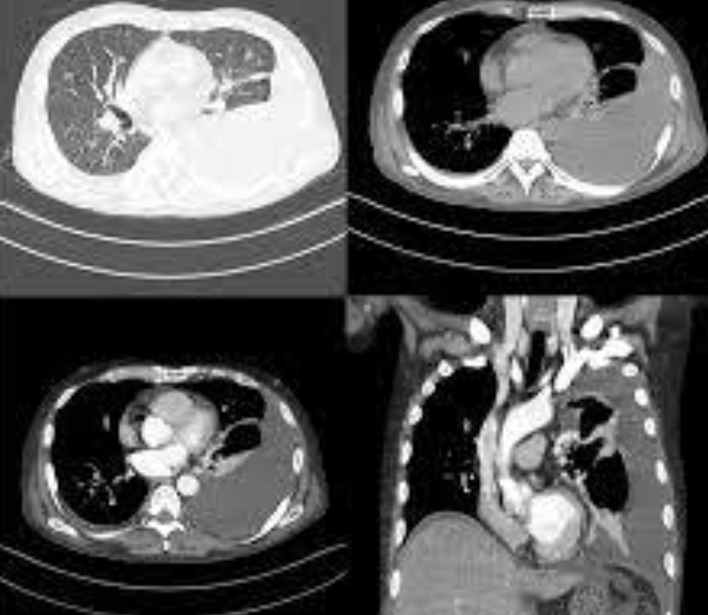

전리방사선 및 비전리방사선의 취급과 방사성동위원소를 이용한 행의학검사와 초음파검사 등 관리 및 취급 업무를 하는 사람을 말합니다. 보통 병원에 가서 엑스레이 검사를 하거나, CT, MRI 검사를 하는 사람들이 방사선사이고, 핵의학과, 방사선종양학과에서 일하는 사람도 방사선사입니다.